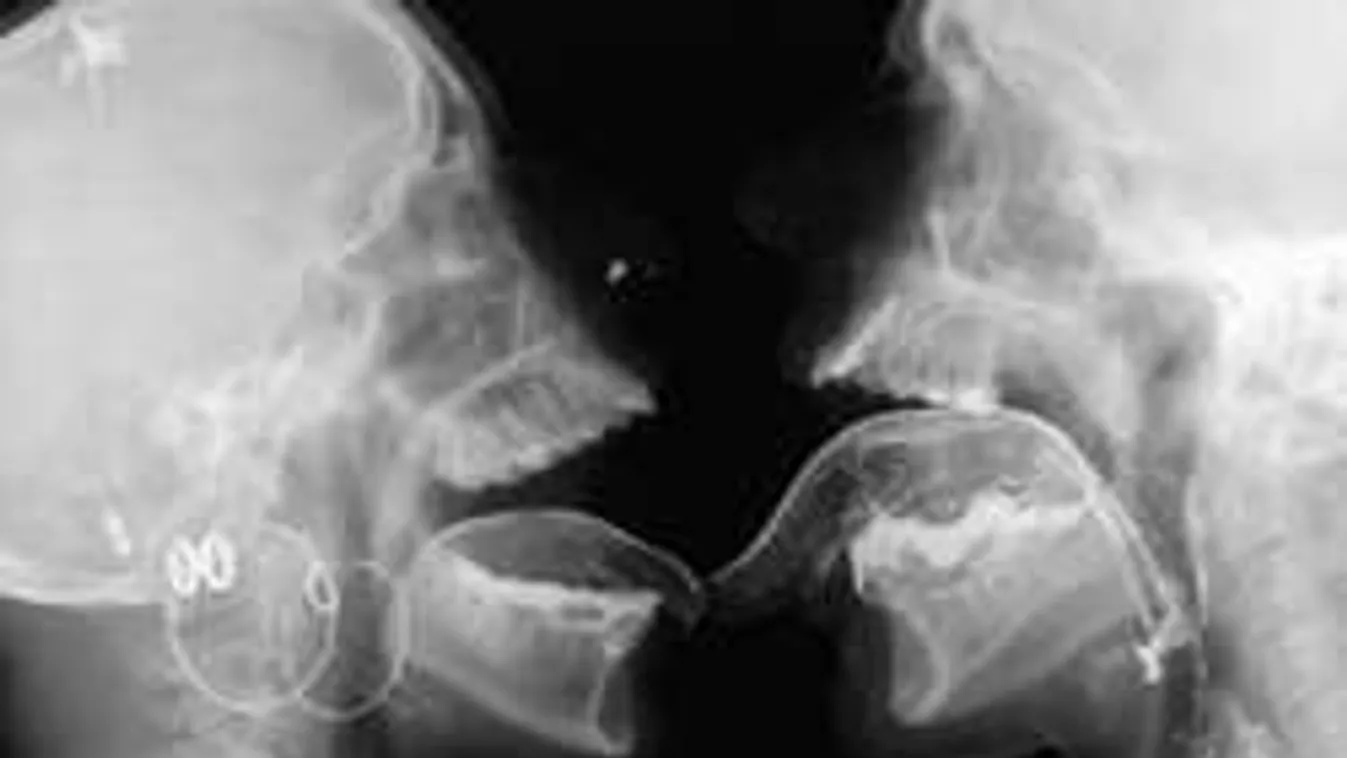

Nemrégiben holland kutatók bebizonyították, hogy nem csak egészségügyi problémák szűrésére jó a röntgen vagy az MRI készülék. A tudósok ugyanis kíváncsiak voltak arra, mi zajlik a testen belül egy csók vagy épp egy intim együttlét során.

Ezek a készülékek megmutatják azt a világot, amit még sosem láttál. Az orvosok pedig pontos képeket kaptak arról, hogy működik az agy vagy éppen hogy dobog a szív egy-egy hevesebb együttlét vagy épp az orgazmus közben.

A felvétel bizarr, sőt sokak számára ijesztő is.